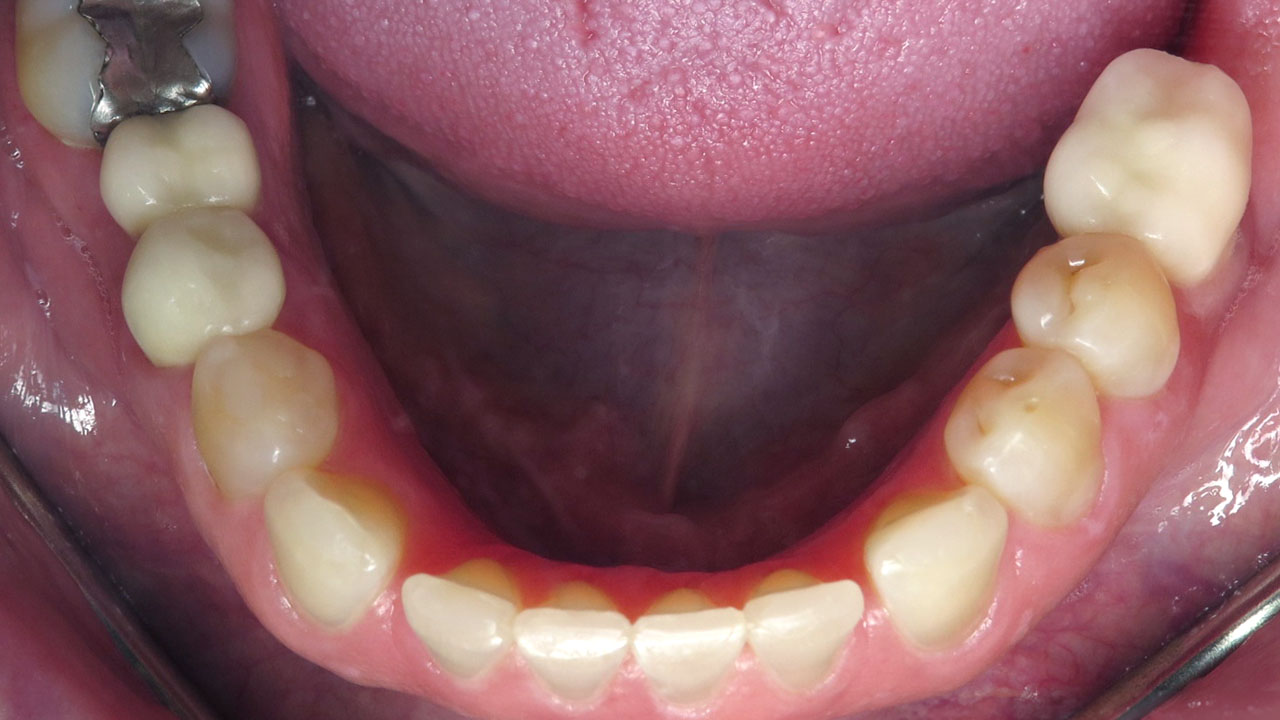

Conservative composite bonding to rebuild and protect the worn edges of the upper and lower front teeth.

Composite bonding on seven upper teeth and eight lower teeth.

The worn edges were rebuilt to protect exposed dentin, improve comfort, and restore a more natural appearance while allowing the patient time to consider more comprehensive treatment options in the future.

Instead, conservative bonding was used to rebuild the worn edges of the upper and lower front teeth. The treatment protected the exposed dentin and improved comfort and appearance while preserving future treatment options.